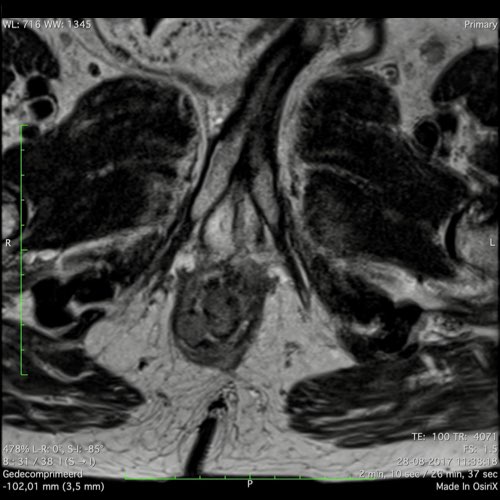

Hình ảnh

Các hình ảnh được cung cấp cho thấy ung thư biểu mô tế bào nhẫn với tình trạng dày lan tỏa thành trực tràng, hình ảnh bia bắn điển hình, và sự xâm lấn mỡ mạc treo trực tràng.